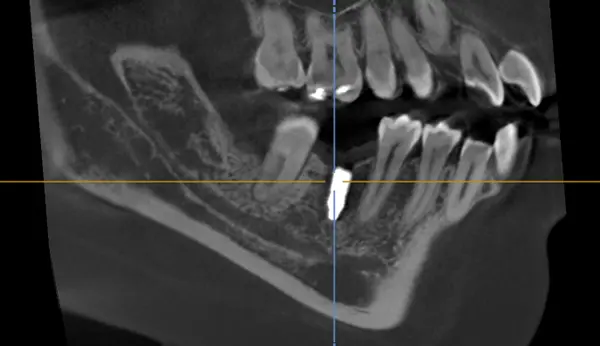

インプラント手術を受けていただく全ての患者様に、術前にC Tを撮影します。患者様の骨の形や神経・血管の走行などを正確に把握し綿密に計画を立てて、安全にインプラント処置を行います。

サイナスリフト法とは、上顎にインプラント(人工歯根)を挿入する場所を確保するため、骨が薄い部分の上顎洞に自家骨や骨補填剤を置き、そこに骨を作顎の骨量を増す治療法です。上の歯のすぐ上には上顎洞と呼ばれる空洞があり、その上顎洞までの骨が薄く上顎にインプラント(人工歯根)を埋入できない場合に行います。

上顎洞側壁骨の相当部の歯茎を切開し、骨に窓を開けて骨片を下から内側に押し上げて上顎洞底部の粘膜を拳上します。次に拳上して出来たスペースに移植材を入れます。移植材を入れた後、外側を特殊な膜で被い歯肉を縫合して6ヵ月間置いて、造骨を待ちます。

上顎洞下のインプラント埋入時における骨造成としてソケットリフトと呼ばれる手法が存在します。

頬骨の奥に存在する上顎洞と呼ばれる空洞に骨移植材を充填して、上顎の骨に厚みを加えるテクニックです。

インプラント体の埋入する穴から移植骨や骨補填材を補填する為、低侵襲で安全に上顎洞の底部分を押し上げることが可能です。また、切開箇所の治癒や骨が仕上がる期間を待つ必要がないので、骨造成とインプラント埋入手術を同時に行う事ができ、その他の骨造成よりも治療期間が短くなるメリットもあります。

具体的な治療内容は、まずインプラントを埋入する位置に、ドリルを使用し上顎洞と骨の間に厚さ約1mm残しながら孔を開けます。ドリルの先にある上顎洞まで貫通させるのではなく、貫通する直前でドリルをストップさせる形になります。そこから専用の器具(オステオトーム)で槌打し、徐々に衝撃を加えながら、上顎洞粘膜に覆われている上顎洞を押し上げていきます。押し上げたスペースに移植材を填入し、インプラントを埋入して終了です。